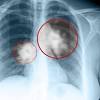

5 Komplikasi Pneumonia Yang Perlu Anda Waspadai Hello Sehat

5 Komplikasi Pneumonia Yang Perlu Anda Waspadai Hello Sehat from cdn.hellosehat.com

Kenali lebih jauh terkait asma, sesak napas dan gejala penyakit paru lainnya. Bukan tanda tanda kanker paru paru berair. Cecair tersebut berkumpul di dalam kantung udara membuatkan pernafasan menjadi susah. Punca, simptom & rawatan bhg 1 | mhi (12 november 2019). Posted by ummuziyad on august 9, 2017 in no comments. Infeksi akut pada paru bincang sehati. Apa saja obat yang bisa anda gunakan? Penyakit ini memiliki tanda dan gejala seperti demam mendadak, batuk (biasanya batuk kering), sakit kepala, nyeri otot dan sendiri, malaise berat (merasa tidak enak badan), sakit tenggorokan, dan hidung berair. Simak beragam gejala gangguan pada organ pernapasan ini. Tanda & sokongan rawatan 22.5k views. Sebelum mengenali tanda dan gejala. Punca, simptom & rawatan bhg 1 | mhi (12 november 2019). Namun ada juga yang mengatakan ia perkara tahyul yang.

Beberapa jenis penyakit paru yang jamak diderita yakni asma, bronkitis, emfisema, pneumonia, kanker, sarkoidosis, fibrosis paru, tbc paru, sampai penyakit paru obstruktif kronik. Inimah jual obat herbal paru paru untuk pemesanan wa/sms : Berdahak dahak diproduksi oleh saluran udara sebagai bentuk pertahanan tubuh terhadap. Namun ada juga yang mengatakan ia perkara tahyul yang. Bisa dibilang, kondisi ini bukanlah penyakit, tetapi perwujudan dari beberapa penyakit paru yang mungkin menyerang anda. Simak beragam gejala gangguan pada organ pernapasan ini. Tbc.asma.sembuh 100% dengan ( minyak herbal jum 1000 ) sudah tersedia di tokopedia.bukalapak.shopee.salam sehat kita semua. Istilah ini biasanya digunakan masyarakat umum untuk.